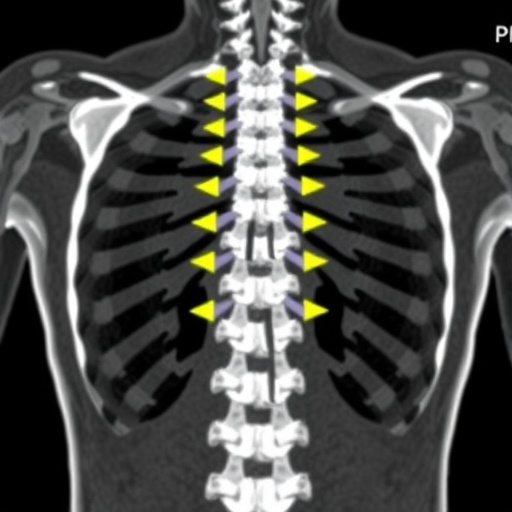

The bamboo spine phenomenon — characterized by the calcification and fusion of spinal segments in AS patients — can often obscure traditional evaluation methods, leading to a potential underestimation of osteoporosis risk. By employing a CT-based analysis and focusing on Hounsfield units, the researchers observed a marked improvement in diagnostic accuracy. It appears that this imaging technique allows for a more nuanced view of the bone architecture, which is essential in the correct classification of osteoporosis in patients with distinctive spinal deformities.

Recent advancements in medical imaging have opened new avenues for the assessment of osteoporosis, particularly in challenging patient populations such as those suffering from ankylosing spondylitis (AS). A pivotal study has emerged, indicating that the use of Hounsfield units (HU) derived from computed tomography (CT) scans may enhance the identification of osteoporosis over traditional dual-energy X-ray absorptiometry (DXA) techniques. This groundbreaking work, which focuses on patients exhibiting a radiological feature referred to as “bamboo spine,” presents a compelling argument for a paradigm shift in how we evaluate bone density and, consequently, osteoporosis risk.

The study in question employed a CT-based approach utilizing a HU cut-off value of less than 135 to classify patients more effectively. The results revealed that a staggering additional 78% of patients were classified as having osteoporosis when compared to the classifications provided by DXA scans. This discrepancy highlights the insufficiency of DXA evaluations for those with complex spinal conditions, where the conventional assessments fail to capture the nuances of bone density variations.